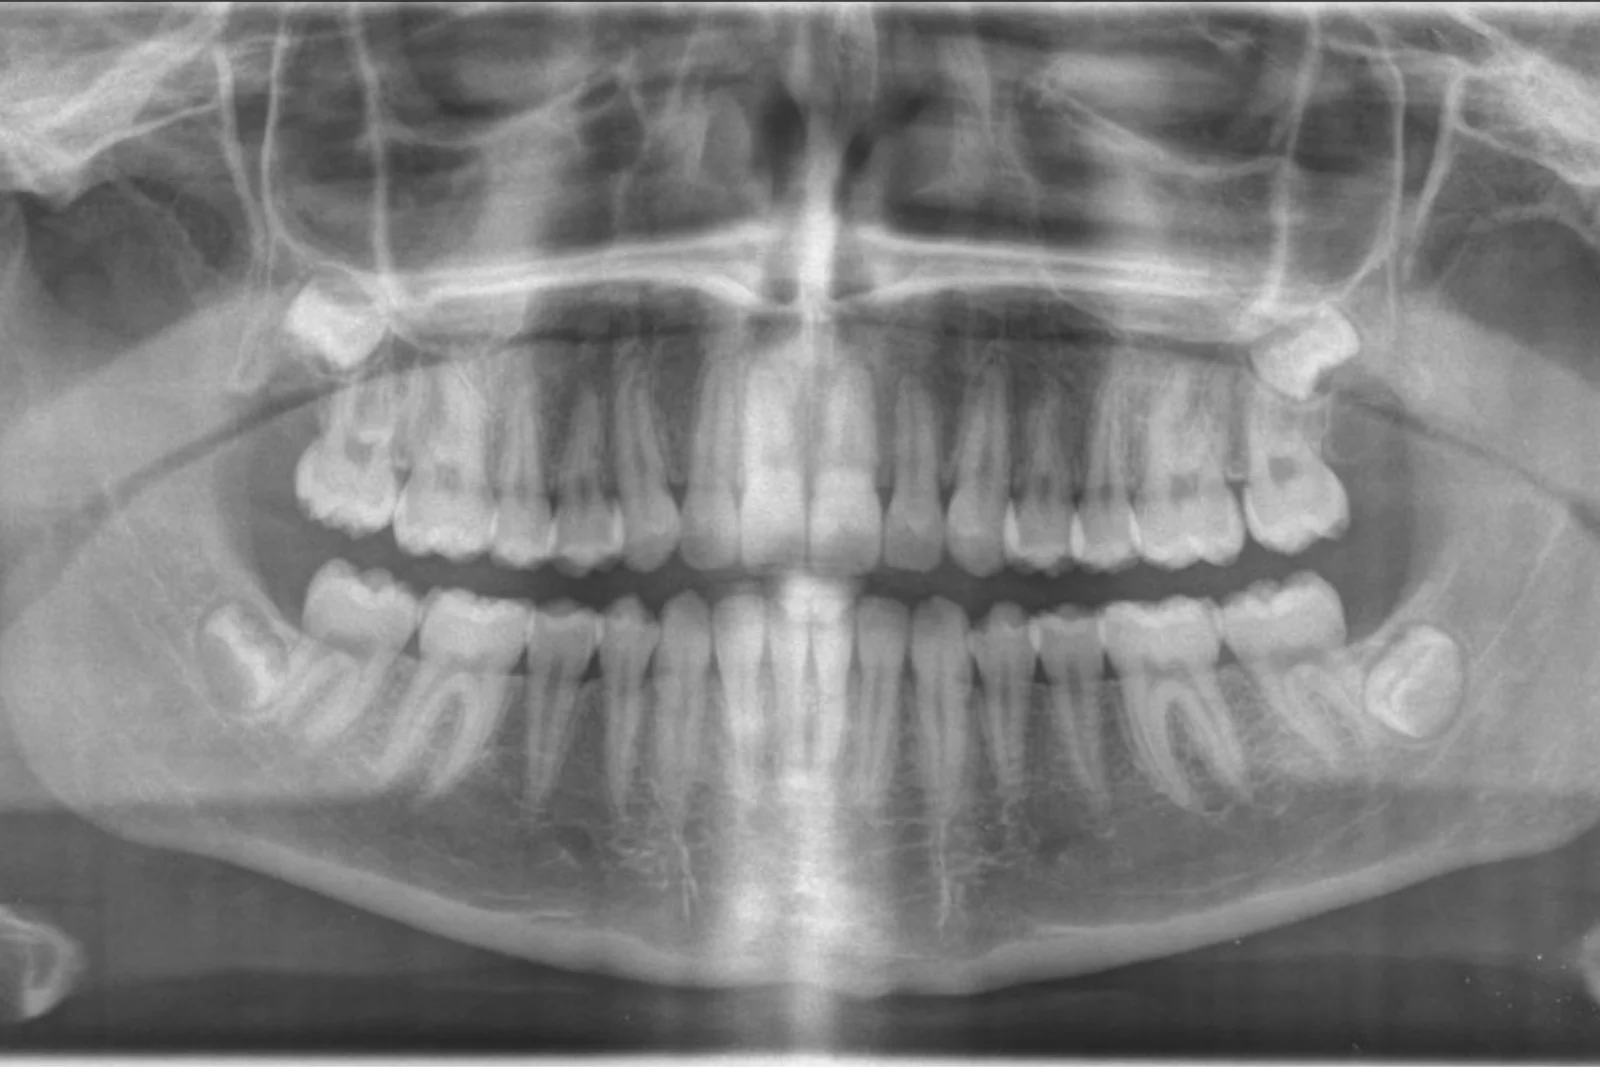

Panoramique + Cone beam

Nous réalisons au cabinet l’imagerie qu’elle soit 2D ou 3D, aide au diagnostic, à la planification pour la pose d’implants et à l’extraction de dents de sagesse complexes.